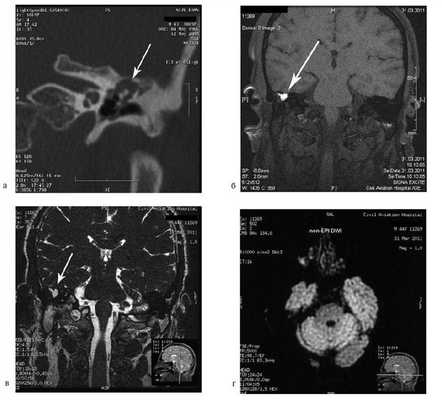

Рис. 1. КТ височных костей пациентки М. а — коронарная проекция: деструктивная полость в пирамиде височной кости, заполненная субстратом неоднородной плотности, капсула лабиринта значительно разрушена на уровне базального и апикального завитков улитки, латерального и верхнего полукружных каналов; б — аксиальная проекция: деструктивная полость с разрушением задней грани пирамиды, передневерхней и нижней поверхности.

По результатам МРТ головного мозга правая пирамида височной кости деформирована, увеличена в объеме, выполнена субстратом размером до 5,5—2,8—3 см, распространяющимся на область внутреннего слухового прохода, заднего полукружного канала, медиальные отделы барабанной полости, сосцевидный отросток. Описанный субстрат изо-гипоинтенсивен в режиме Т1, гиперинтенсивен — в Т2 и non-EPI DWI (рис. 2). Заключение: признаки рецидива холестеатомы с деструктивными изменениями структур внутреннего и среднего уха на фоне хронических воспалительных изменений.

Рис. 2. Магнитно-резонансная томография головного мозга пациентки М. Деформированная, увеличенная в объеме пирамида височной кости выполнена мягкотканым субстратом.

Пациентке была выполнена МРТ основания черепа по описанной методике (рис. 1). Рисунок 1. МРТ основания черепа больной Ф. с хроническим правосторонним гнойным средним отитом. Фистула лабиринта. Холестеатома. а — исследование в режиме Т1; б — в режиме Т2; в — в режиме non-EPI DWI.

На КТ височных костей справа послеоперационная полость, заполненная мягкотканным образованием, определяется большой костный дефект в направлении сигмовидного синуса и мозжечка (рис. 2, а). Рисунок 2. КТ и МРТ височных костей больной У. с хроническим правосторонним средним отитом. Состояние после радикальной операции (1993 г.), санирующей операции с мастоидопластикой и тимпанопластикой (2003 г.). Холестеатома. Парез лицевого нерва. а — КТ; б — МРТ основания черепа в режиме Т1; в — в режиме Т2; г — в режиме non-EPI DWI.